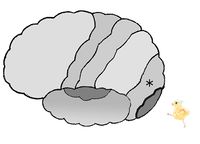

図は、左の大脳皮質を左から見た図です。

中心溝の前にある中心前回には、運動野があります。「手を挙げよう」などの随意的運動の命令は、前頭葉の中心前回に発生し、上肢、肩の筋へ届けられ手が挙がります。

中心溝の後ろにある中心後回には、(皮膚)感覚野があります。頭頂葉の一部です。皮膚から触圧覚・関節の感覚の情報は頭頂葉の中心後回に届いて「触った!」と感じるのです。

大脳皮質の図において、*印は 前頭葉 頭頂葉 後頭葉 側頭葉 である。

大脳皮質の図において、*印は 中心前回 中心後回 である。

大脳皮質の図において、*印は 中心前回 中心後回 である。